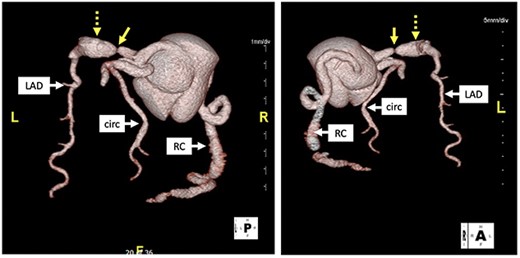

Computed tomography with 3D reconstruction. Solid yellow arrow points to tight stenosis in the left anterior descending and dotted yellow arrow points to post-stenotic aneurysm.

His initial troponin was not elevated although the electrocardiogram showed new ST depressions in the medial precordial leads and subsequent troponins were elevated. He was transferred to our institution and underwent left heart catheterization which demonstrated a right dominant circulation with ectasia of the right coronary artery, a fusiform aneurysm of the left anterior descending coronary artery (LAD) and a generous-sized left circumflex coronary artery (Fig. 1). There was a 99% stenosis of the LAD with post-stenotic dilatation up to 13 mm with gradual normalization over the course of the remainder of the vessel. An echocardiogram showed a left ventricular ejection fraction of 35% without valvular pathology. Percutaneous coronary intervention (PCI) was thought to be a poor option because the distal portion of the stent would not oppose the wall of the vessel but be ‘floating’ in the aneurysmal portion of the artery pre-disposing thrombus formation. Therefore, in anticipation of operative intervention, a computed tomography scan was done to further define the anatomy. The scan demonstrated extensive wall thickening and contour irregularity suggestive of diffuse coronary arteritis (Fig. 2). The study also showed a dilated main pulmonary artery up to 46 mm and an aberrant right subclavian artery coming off the distal aortic arch and passing behind the esophagus.